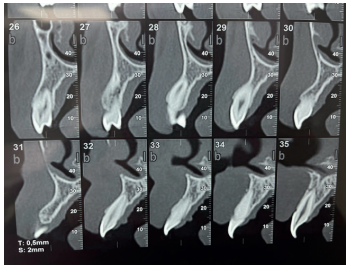

Como prueba complementaria se solicitó un estudio CBCT, en el que se observaron signos de fractura leve de la cortical vestibular en la zona del incisivo central superior derecho, a nivel del tercio medio radicular (Figura 4), por lo que se procedió a realizar la ferulización de todo el sector anterosuperior (Figura 5).